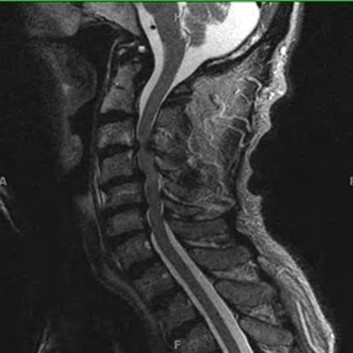

급성 디스크 손상 및 디스크 탈출증

허리 디스크에 의한 급성 통증 발생 시에도 심부신경 주사치료를 통해 효과적으로 통증을 조절 할 수 있습니다. 갑작스런 자극에 의한 신경의 통각 과민을 예방하고 붓고 파열 된 디스크의 크기를 줄임으로써 수술 없이 안전하게 치료가 가능합니다. 효과적인 치료를 위해 반복해서 치료 해야 합니다. 심각한 디스크의 파열은 수술이 필요 할 수도 있습니다.

척추관 협착증의 치료

좁아진 척추관에 의해 발생한 협착증은 심한 경우 주사로 좁아진 공간을 넓게 할 수 없습니다. 다만 심부신경주사치료를 통해 척추관을 효과적으로 감압 할 수 있으며 신경에 대한 주변 조직의 압박을 줄이고 자극과 유착을 제거 합니다. 주사로 해결 되지 않는 경우 신경성형술 등의 시술을 고려 할 수 있으며 운동신경손상 및 통증 정도에 따라 수술을 시행 해야 하기도 합니다.